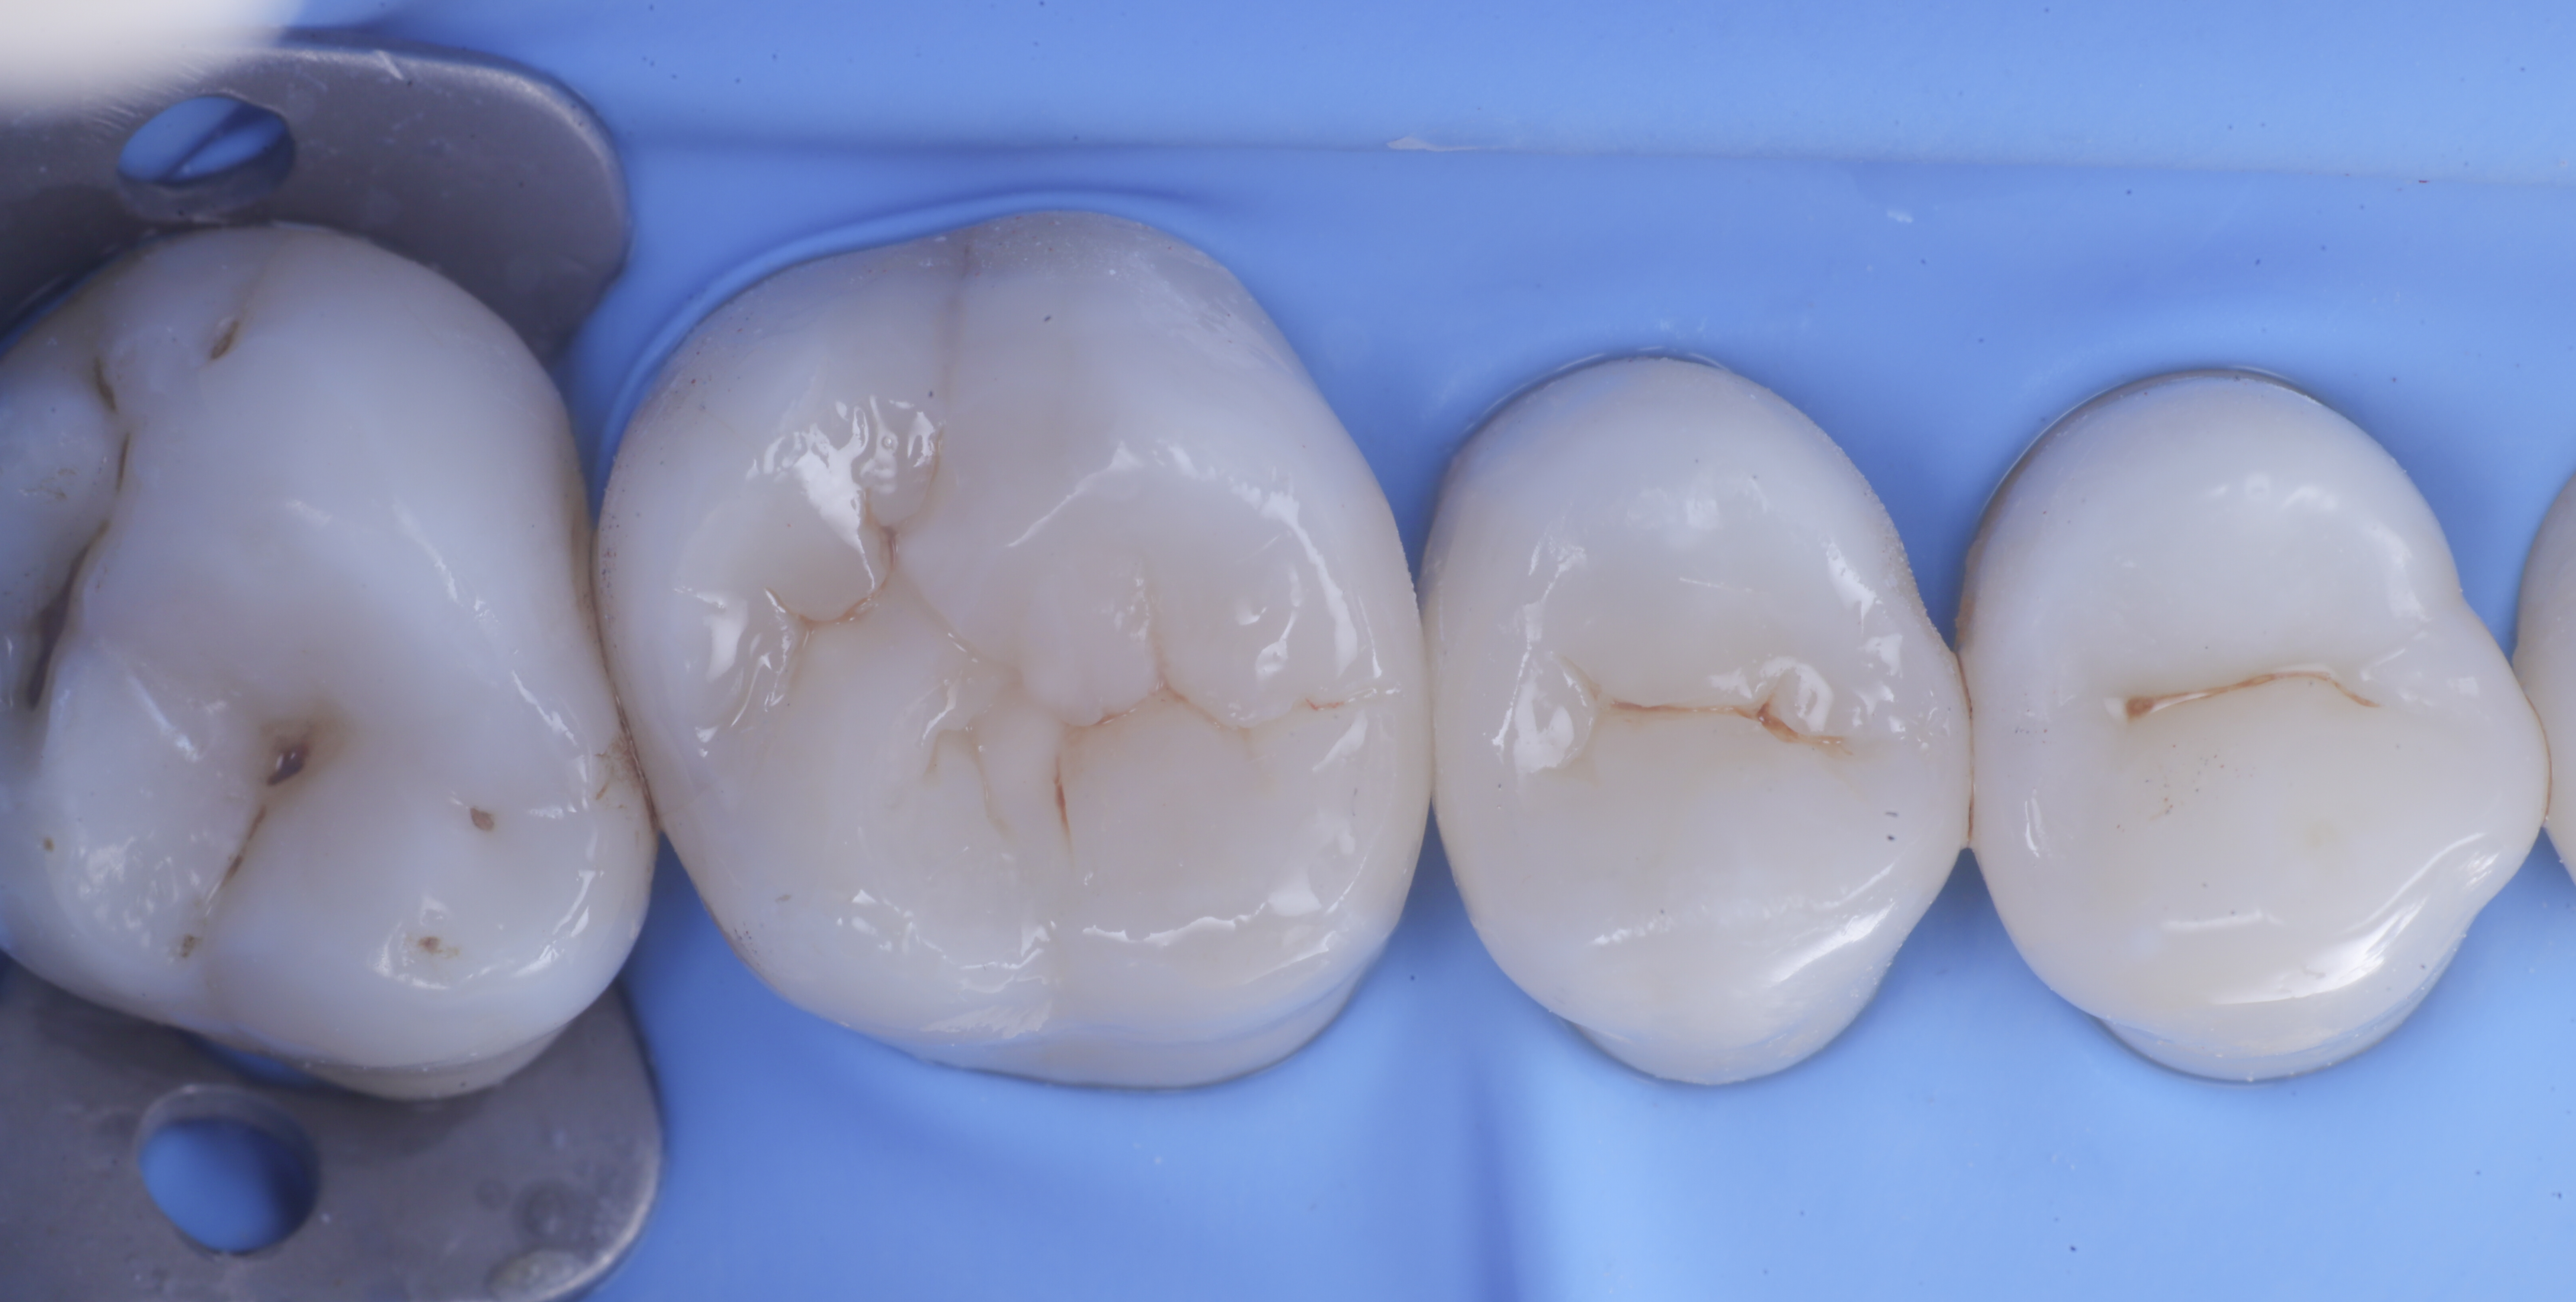

foto 6 Aspetto occlusale delle pareti interprossimali appena create

foto 7 Aspetto vestibolare delle pareti interprossimali appena create

foto 8 Modellazione ed aspetto occlusale

foto 9 Modellazione ed aspetto vestibolare

foto 10 Modellazione ed aspetto palatino